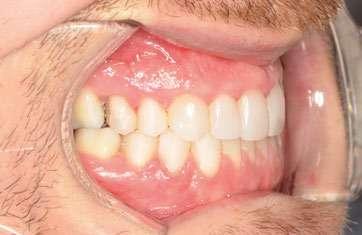

2. Análisis intraoral (Ilustración 2 y 3):

 Clase III molar y canina de Angle bilateral.

 Mordida abierta anterior > 3 mm.

 Compresión maxilar junto con mordida cruzada posterior bilateral.

 Línea media inferior desviada 2 mm hacia la derecha.

Ilustración 2. Fotografías intraorales iniciales de estudio.

Tras 18 meses de tratamiento, se concluyó la fase ortodóncica y se colocaron las carillas de composite definitivas de canino a canino en la arcada maxilar, obteniendo los siguientes resultados:

1. Expansión maxilar efectiva junto con mejoría en la estética de la sonrisa (Ilustración 10):

 Se corrigió la mordida cruzada posterior bilateral disminuyendo los corredores bucales.

2. Corrección de la mordida abierta anterior (Ilustración 11):

 Extrusión controlada de los incisivos con alineadores y attachments.

 Reducción de la mordida abierta de 3 mm, logrando una sobremordida adecuada.

3. Mejora de la relación oclusal:

 Conversión de la relación molar y canina de Clase III a Clase I funcional.

 Centrado de las líneas medias.

Ilustración 10. Registros extraorales e intraorales finales.